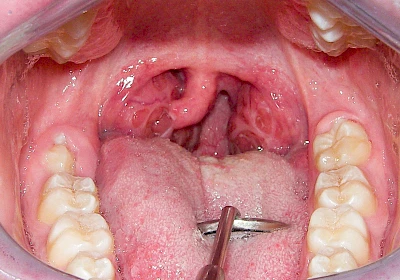

Mandelentzündung

Mandelentzündungen (Tonsillitis) zeigen häufig Rötungen, Schwellungen oder eitriges Sekret im Bereich der jeweiligen Mandel und sollten direkt ärztlich abgeklärt werden. Vielen Menschen wurde vor allem in der Kindheit ein- oder beidseitig die Mandeln entfernt, um die Atmung zu erleichtern. So können im Bereich der Gaumenbögen Vernarbungen oder Seitenunterschiede auffallen. Zudem können nach Mandelentfernungen (Tonsillektomie) die Infektanfälligkeit erhöht sein, da die Mandeln ja Bestandteil der Immunabwehr sind.

Bei Vergrößerung der Gaumenmandeln (Hyperplasie) z. B. infolge chronischer Entzündungenkann die Belüftung der Ohren gestört sein und es kann zu Schnarchen mit Atemaussetzern (Apnoe) sowie zu Schluckstörungen kommen. Bei entsprechenden Auffälligkeiten sollte eine ärztliche Abklärung erfolgen.